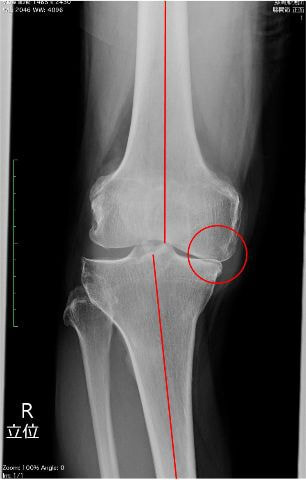

外来通院での運動療法と関節注射を継続して行っていましたが、レントゲンでは膝関節内側の関節軟骨がすり減って、上下の骨が衝突しており、痛みも強いことから手術適応となりました。(左写真)

術後3日目から松葉杖歩行を開始しました。人工膝関節置換術後はO脚が改善し(右写真)、右脚に体重をかけて歩くことも早期に可能になります。術後5日目には、松葉杖を使用せずに両脚で歩くことが可能になりました。入院中は下肢筋力強化練習や歩行練習を反復することにより、日に日に歩行が安定して行えるようになります。